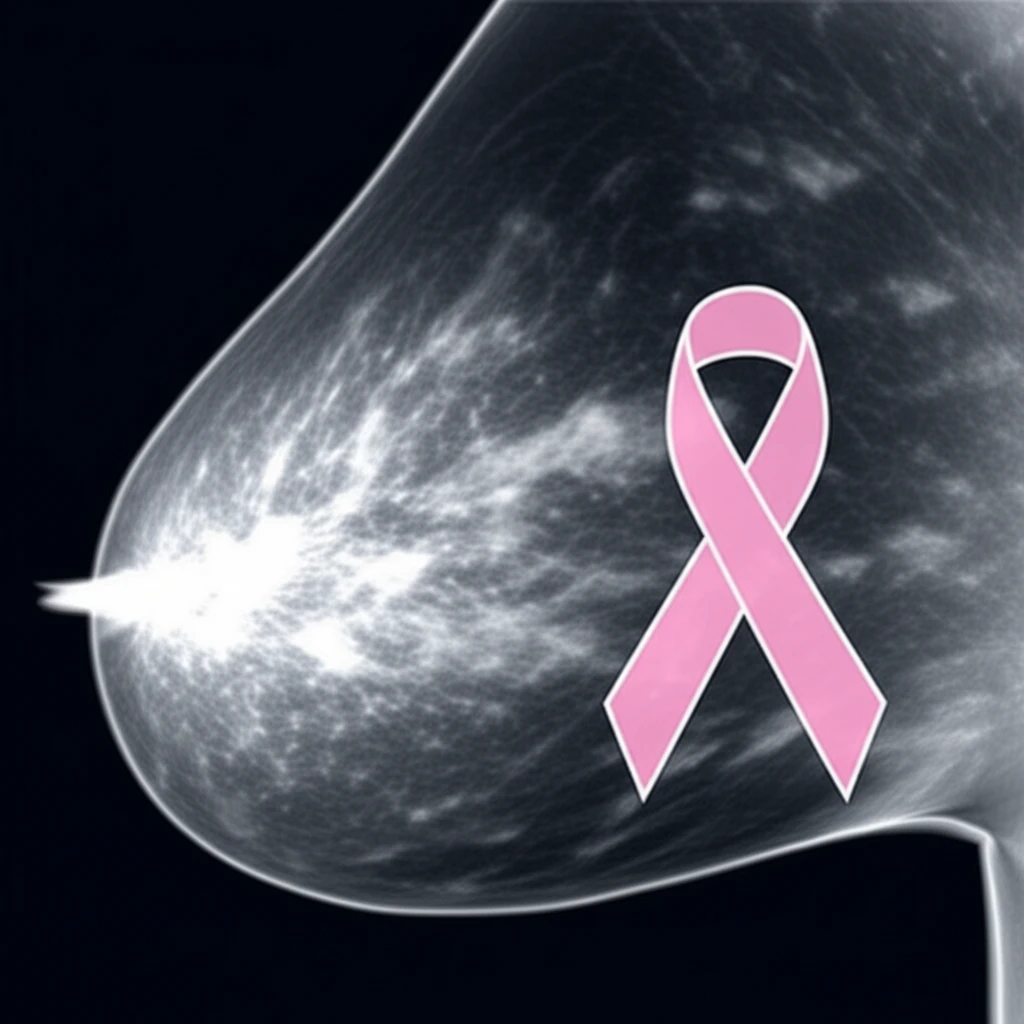

Breast cancer screening is a critical aspect of women's health, and mammography remains a cornerstone of early detection. However, interpreting mammograms isn't always straightforward. One factor that significantly influences the accuracy and effectiveness of mammograms is breast density. Understanding what breast density means, how it's measured, and its implications for cancer risk is essential for informed decision-making.

Mammographic density refers to the amount of fibrous and glandular tissue compared to fatty tissue in the breast. Breasts with higher density have more fibrous and glandular tissue, making it harder for radiologists to detect tumors on mammograms. This is because both dense tissue and tumors appear white on mammograms, potentially masking the presence of cancerous growths.

Recent research published in 'Radiology' delves into the nuances of mammographic density and its association with breast cancer risk. The study compares different methods of measuring breast density and evaluates their effectiveness in predicting cancer risk. This article will break down the findings, offering a clear and accessible explanation of the science behind breast density and its role in breast cancer screening.